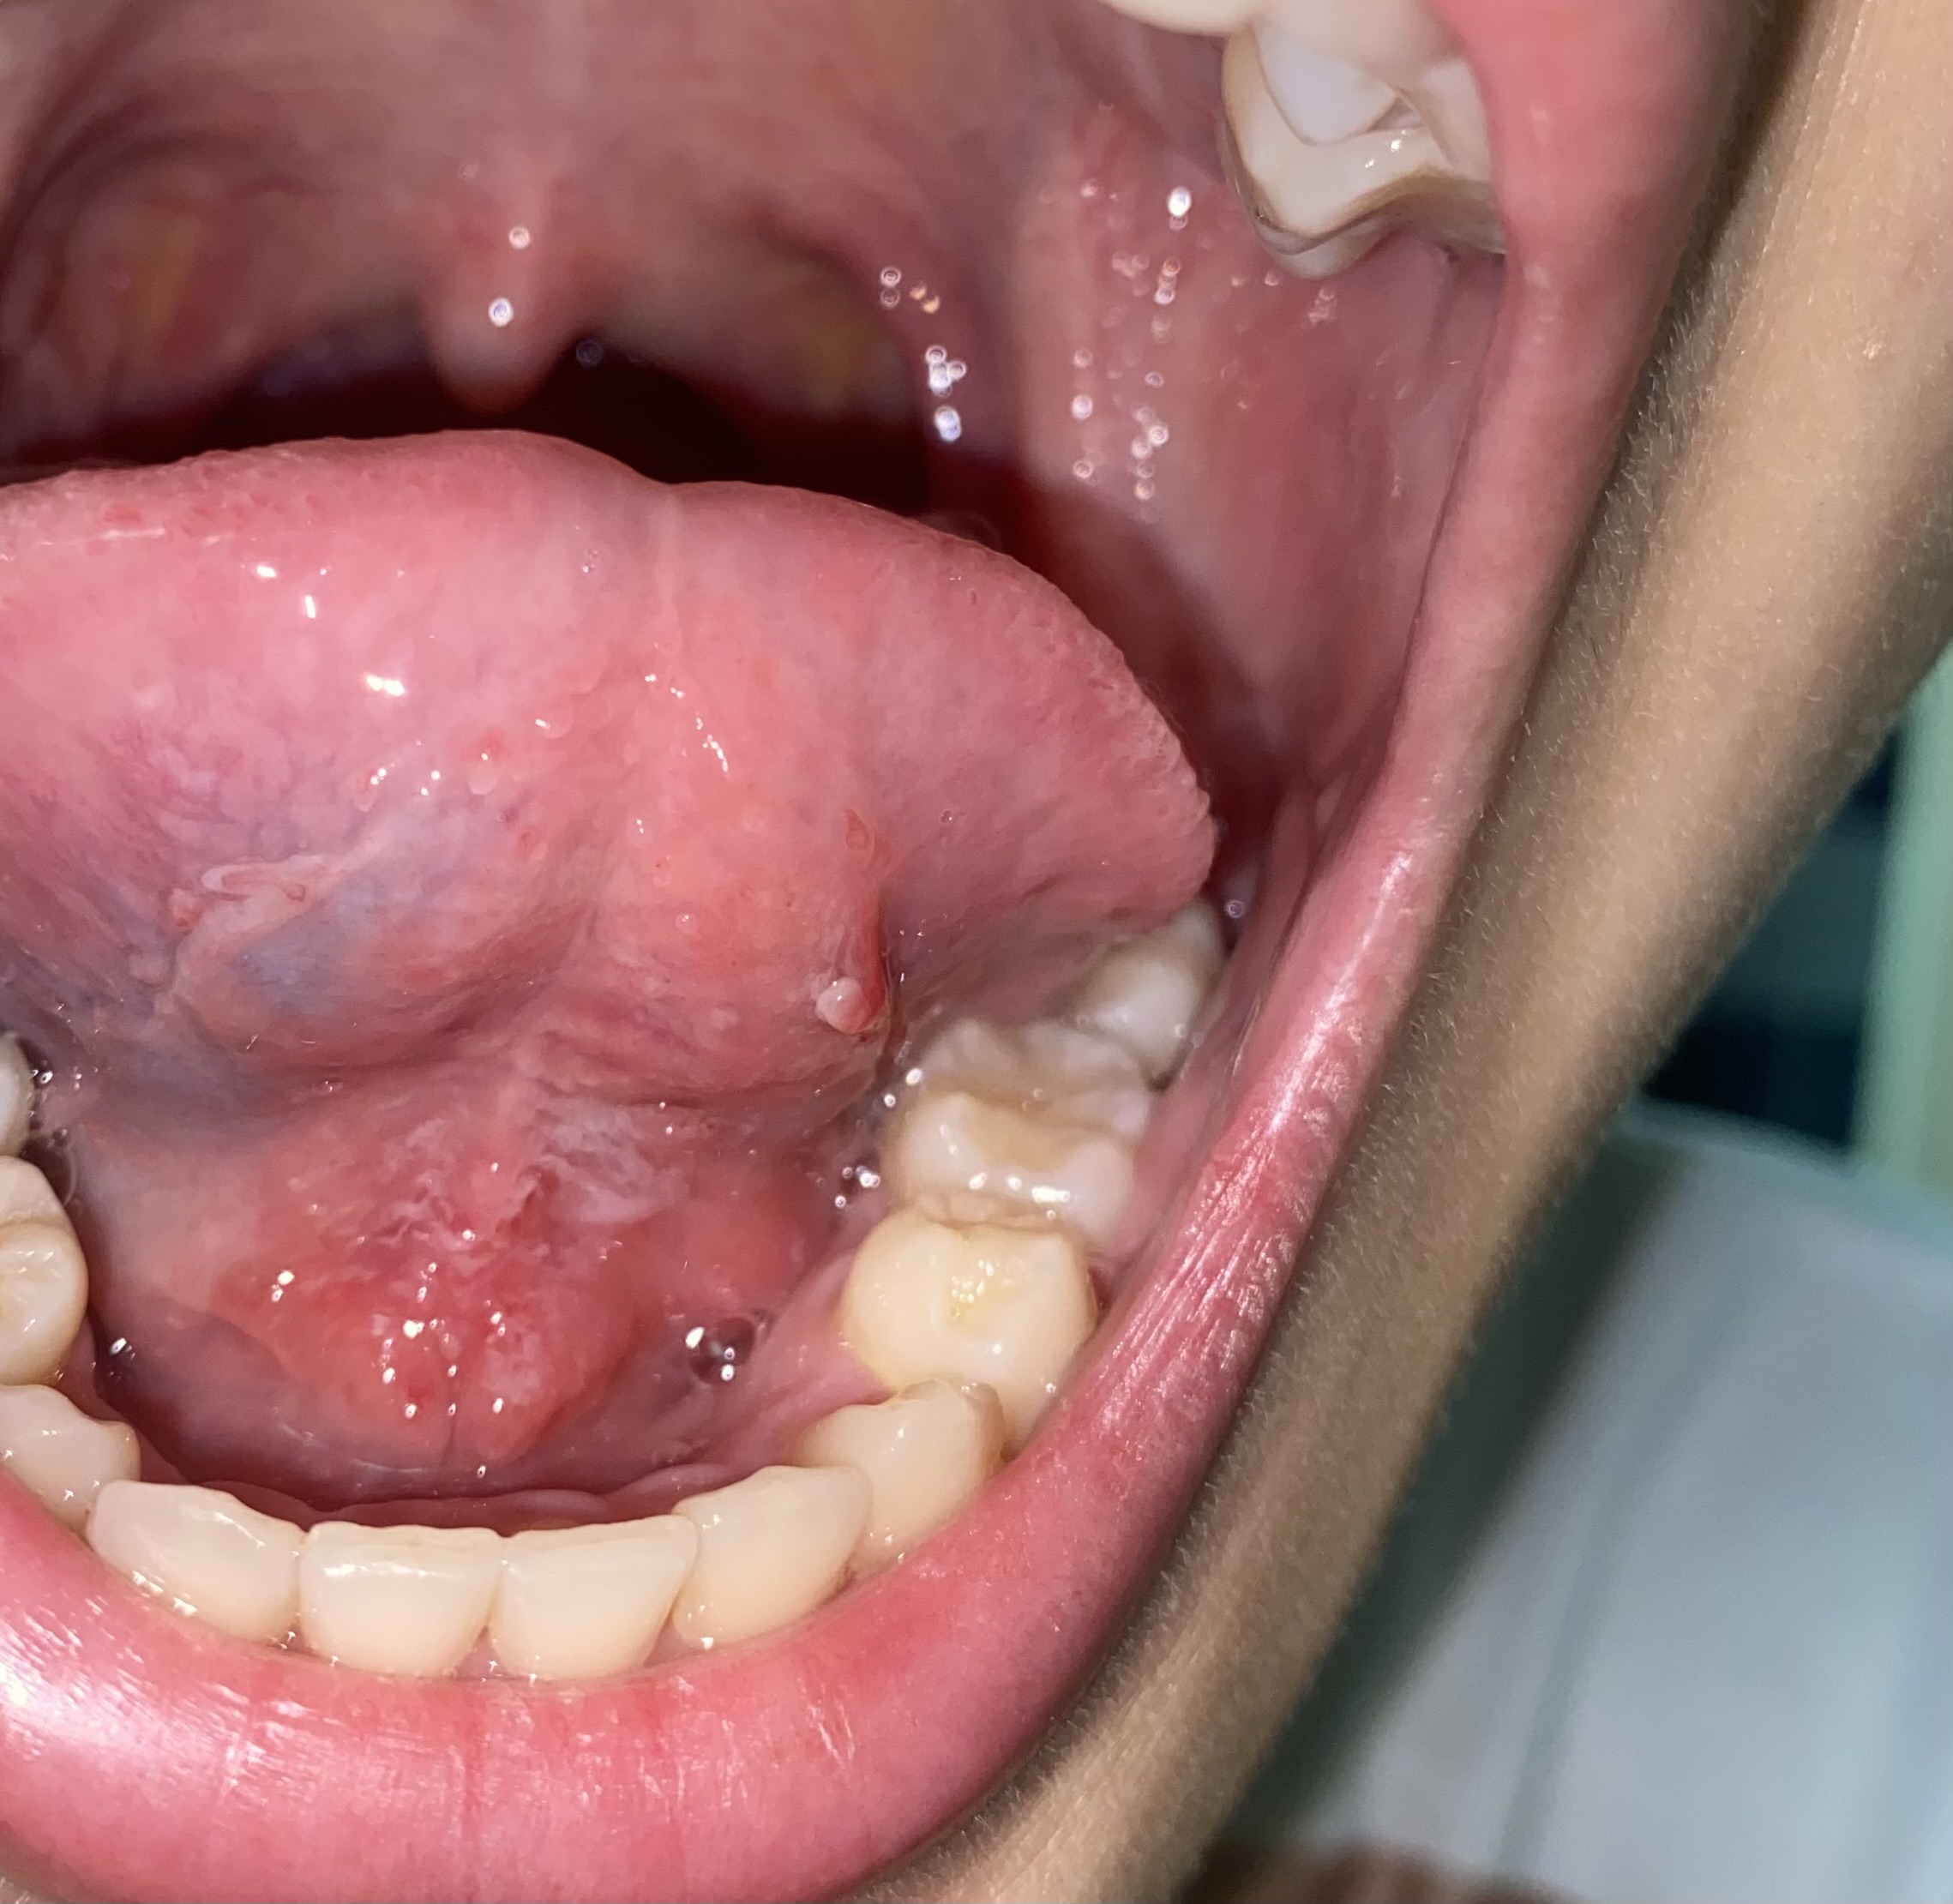

มีอาการมา 5 วันแล้ว วันศุกร์พังผืดใต้ลิ้นเริ่มบวมแดง วันอาทิตย์ ไปหาหมอหู คอ จมูก หมอให้ยาแก้อักเสบ แคปซูลฟ้าเขียวกับยาcemol แต่ก็ยังมีอาการบวมเรื่อยๆ จนไม่เห็นเส้นพังผืดแล้ว วันอังคารตื่นมาริมฝีปากบนมีเลือดเป็นจุดๆ เหมือนช้ำข้างใน เป็นคนใส่รีเทนเนอร์ด้วย เวลาพูดเจ็บมาก เพราะลิ้นไปโดนรีเทนเนอร์ ทำยังไงดี กังวลมาก กลัวจะเป็นโรคร้ายแรง

จากภาพที่คุณส่งมาไม่ใช่มะเร็งครับ มีลักษณะผิดปกติในบริเวณใต้ลิ้นและริมฝีปากด้านใน เช่น:

1. บริเวณใต้ลิ้น

• มีอาการแดง และมีตุ่มนูนเล็กๆ สีขาวหรือใสกระจายอยู่

• บางจุดคล้ายมีเส้นเลือดฝอยโป่งพอง

2. ริมฝีปากด้านใน

• มีอาการบวมแดง โดยเฉพาะบริเวณริมฝีปากล่าง

• มีรอยแดงและจุดเล็ก ๆ ที่อาจเป็นตุ่มหรือจุดเลือดออกใต้ผิว